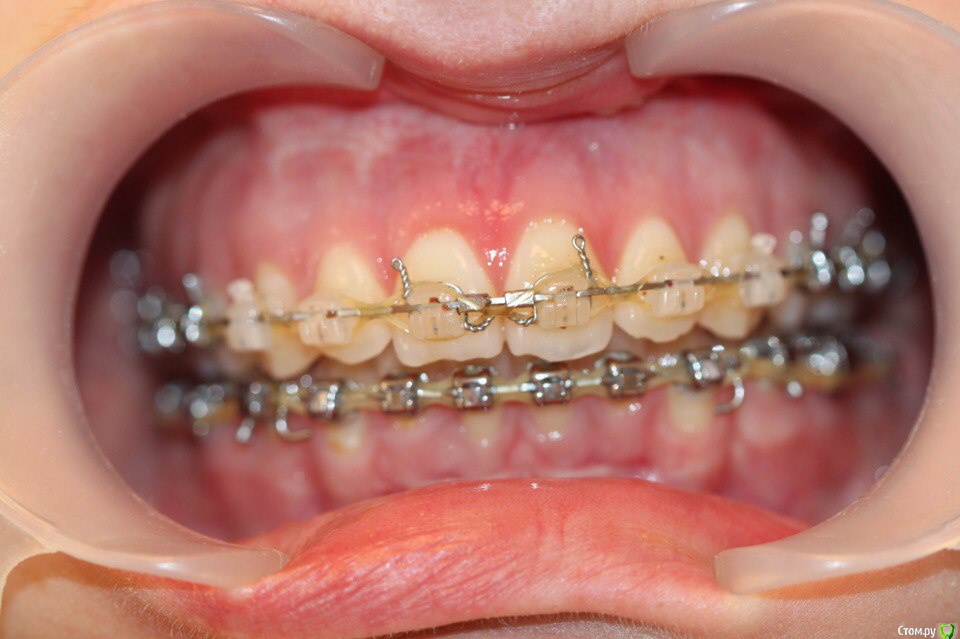

annurka Опубликовано 12 сентября, 2017 Поделиться Опубликовано 12 сентября, 2017 (изменено) здравствуйте! 24 года, дисфункция ВНЧС, дистальный прикус (1,4см), ортодонтическое лечение начато с ношения каппы для разгрузки сустава (привыкла подтягивать НЧ к верхней) в 2012 году. проведено лечение: удаление всех 8к (непрорезавшиеся), расширение ВЧ (аппарат дерихсвайлера), выравнивание зубных рядов, сепарация нижних резцов (резцы были наклонены), места не хватило - удаление 2 нижних 4к, выравнивание кривой шпее, двухчелюстная остеотомия; выравнивание окклюзионных контактов (резиновые тяги) проблема: между верхними и нижними резцами расстояние 5мм к трг (внизу фото) есть расшифровка.все идет к снятию брекетов, и с эстетической точки зрения меня все устраивает. но не до конца устраивает в функциональном плане (я не могу пропихнуть палец между зубными рядами, как раньше, но все также подтягиваю челюсть кпереди когда ем, говорю)стараюсь контролировать это, но даже улыбнуться не могу не подтянув - иначе у меня некрасиво вырисовывается подбородок, неправильно произношу звуки при разговоре.сразу после остеотомии состыковка резцов была ок - нижние зубы были за верхними, но мы с ортодонтом занялись состыковкой и других зубов (которые тогда не соприкасались), и когда добились контактов жующих сторон, разошлись резцы.UPD: и еще есть черные треугольники на НЧ - с ними тоже очень хочется разобраться лечащий ортодонт говорит, что это в целом норма, с учетом моего случая. и возможно это так, но я очень хочу послушать еще мнений, возможно стоит удалить 2 зуба наверху, чтобы верхняя челюсть подошла по размер нижней? [боюсь что простой сепарации может не хватить и как в случае с нижними резцами придется и сепарацию делать, и удалять зубы.] может быть еще есть другой способ добиться нормального прикуса, без "нюансов"?изначально я пошла на все это лечение, чтобы остановить разрушение сустава (однажды проснулась и не смогла рот даже открыть, еще до лечения), полагала, что брекеты и члх исправят если не ситуацию, то причину, но я все еще двигаю НЧ вперед к ВЧ. с остеотомии прошел почти год (поэтому на изменение картины эластиками я уже не надеюсь), брекеты ношу почти 4 года. заранее всем спасибо за отклик! Изменено 12 сентября, 2017 пользователем annurka 1 Ссылка на комментарий

annurka Опубликовано 13 сентября, 2017 Автор Поделиться Опубликовано 13 сентября, 2017 (изменено) А До лечения есть ТРГ посмотреть? И фото какие-нибудь?есть трг сверху - сразу после остеотомии, снизу - через полгода после (когда резцы отошли друг от друга на 5мм) до лечения вообще точно делал ортодонт (снимки, слепки, фото), если в клинике это сохранили, я смогу сфотографировать. далее фото в процессе лечения - 4ки нижние еще не удалены, один хирург был готов так оперировать, другой сказал, что наклон нижних резцов неправильный и нужно как и было запланировано удалить 4ки, сепарации недостаточно.челюсть расслаблена как есть: НЧ подвинута к ВЧ для наглядности: есть фото слепков того периода, но форум ругается на слишком большой размер. если нужно - уменьшу залью) Изменено 13 сентября, 2017 пользователем annurka 1 Ссылка на комментарий

annurka Опубликовано 13 сентября, 2017 Автор Поделиться Опубликовано 13 сентября, 2017 (изменено) вот трг до начала лечения, фото к сожалению нет, если только из жизни) расшифровка трг ДО (где выделено синей ручкой) и недавнее Конечно контакты не идеальны, но если удалить 4ки наверху нижняя треть лица будет иметь довольно вогнутый вид спасибо за комментарий! а если сделать сепарацию резцов, тогда получится избежать вогнутости профиля? С ДВНЧС у вас сейчас проблемы остались? Можно рассмотреть совместно с врачом аппараты для выдвижения нижней челюсти,если тяги не справляются не было до недавнего времени - сейчас иногда болит в области сустава слева (видимо потому что контакты справа уже есть, а слева в процессе, поэтому нагрузка на челюсть неравномерная ?). до операции (но после начала лечения брекетами) сустав не беспокоил, надеюсь это просто период реабилитации.насчет аппаратов по выдвижению НЧ - спасибо, передам ортодонту.с6нимки к сожалению выполнены в разных клиниках, но мне казалось что если судить по трг через полгода, то НЧ там же, где была закреплена титановыми пластинами сразу после остеотомии (но проблема с резцами тогда уже возникла)... или мне так только кажется и произошел рецидив? думаете ее можно еще двинуть вперед? Изменено 13 сентября, 2017 пользователем annurka Ссылка на комментарий